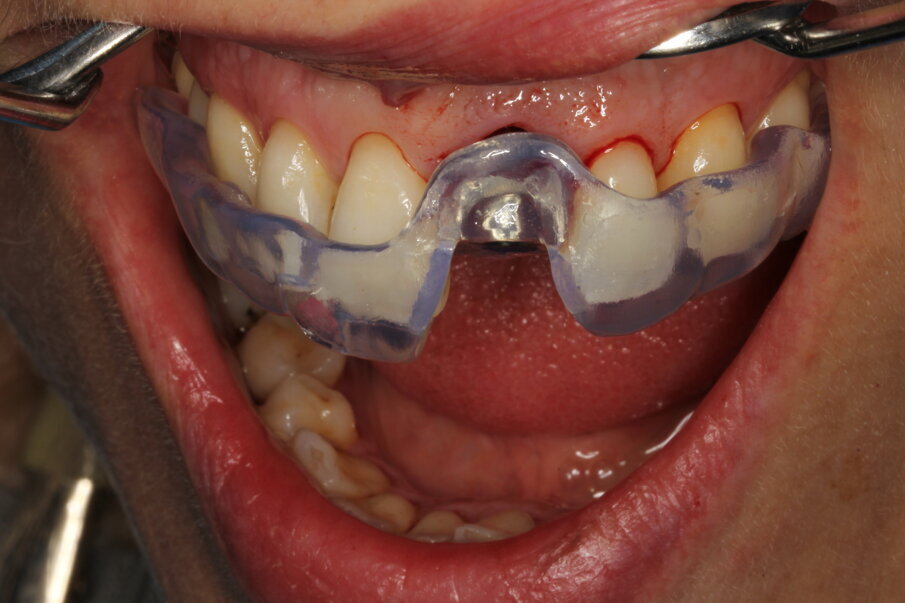

Temporary crown

The surgeon indicated that the healing abutment may be removed after four weeks. By then, the temporary screw-retained crown had already been fabricated by the technician, who had prepared a CAD/CAM-milled acrylic tooth glued on to a Neoss NeoLink abutment (Figs. 27–30). As a result of the decision to place the implant entirely in native bone, the angulation was such as to locate the screw access hole of the provisional on the buccal aspect. This can be easily camouflaged by a simple composite filling after plugging the channel with PTFE tape. The gingival profile copies in this first stage of loading the central incisor anatomy of the Neoss Esthetic Healing Abutment (Fig. 31).